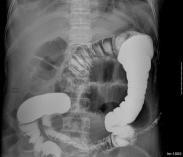

KUB平片:顯示腎實質內呈簇狀,放射狀或多數性粟粒狀排列的鈣化和結石。

IVU:顯示腎盂腎盞正常或腎盞增寬,杯口擴大突出,于其外側見到造影劑在擴大的腎小管內呈扇形、花瓣狀、葡萄串狀和鑲嵌狀陰影,囊腔間不相連。由于結石密度不均勻,邊緣不整齊,環繞于腎盂腎盞周圍的多數囊腔似菜花狀。腎功能不佳者可行大劑量靜脈點滴尿路造影,能更清晰地顯示上述特征。逆行腎盂造影對診斷的作用不大。